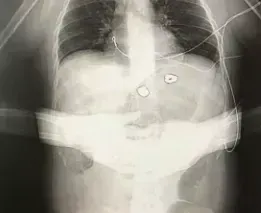

Strangely, although no such X-ray was contained in the medical evidence provided to the Court, one did appear in a LADbible report on the first anniversary of the Manchester Arena incident:

Hibbert told LADbible:

I had two seven-hour operations to remove the nuts and bolts. My feet, legs, arms and jaw were all smashed. One had severed my spinal column. My throat had a part missing. There was one bolt in my face they couldn’t get but it eventually rose to the surface and broke the skin itself. I tweezered it out. I keep it in a jar.

Yet, there is no obvious damage to the arms, throat, or jaw, or of shrapnel embedded in the face, in the above X ray. Nor is the image time-stamped, nor does it identify Martin Hibbert. Moreover, as Hall told the Court,

It cannot be deduced from the X ray, without a lateral view, whether the alleged shrapnel is inside the body, or not. The shrapnel could be on top of the body, underneath the body or possibly even using computer software.

In sum, there is no reason to trust the authenticity of the image.

Tellingly, the claimants did not enter the LADbible X-ray into evidence. They must have known that it would not withstand scrutiny. In which case, why did Martin Hibbert authorise its usage in the first place?